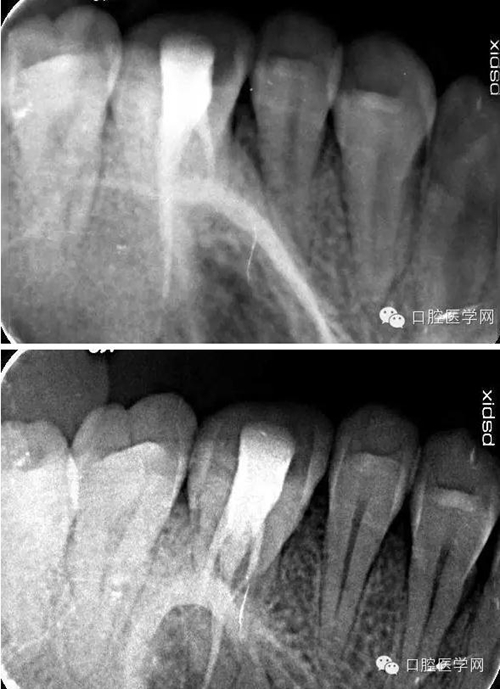

26根尖片可見低密度暗影:

術(shù)中試尖x線片:

術(shù)后x線片: